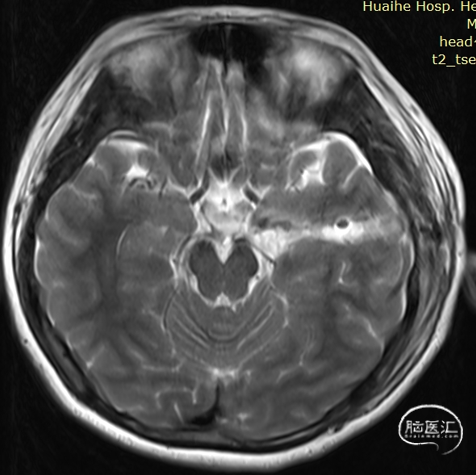

术前检查

术前影像:

左侧海马旁回海绵状血管瘤。